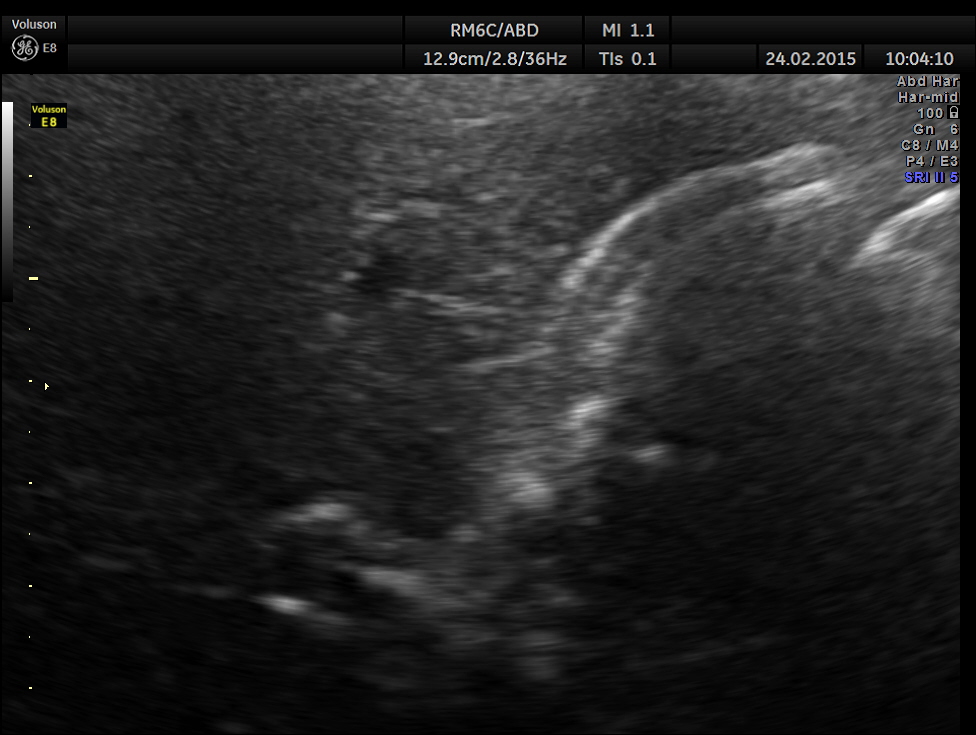

This was a 23 year old young lady , who was evaluated elsewhere for menstrual irregularities . She was reported to have a gallstone . She had no digestive complaints. She went for a 2nd and 3rd opinions, where the gallstone was not seen.She also underwent a CT scan , which reported a shrunk gall bladder and gallstone was not seen. She came to me for another opinion. She was in an over night fasting status ( almost 14 hours after her last meal or drink ).

The following is what was seen.

Completely collapsed and shrunk gall bladder in spite of over night fasting.